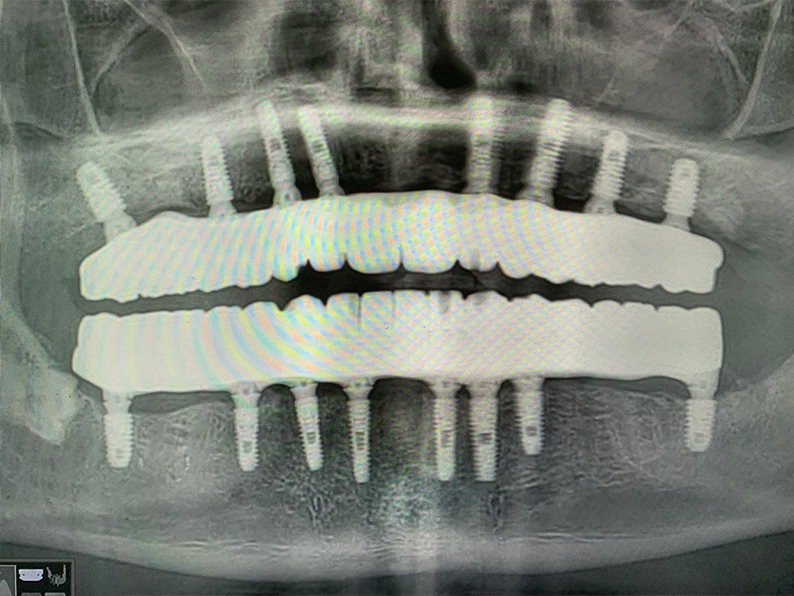

Через год я провел осмотр пациента К. т сделал контрольная ортопантомограмма. На снимке видно, что костная ткань сохранена в полном объеме. Пациент очень доволен итогом лечения, у него нет никакого дискомфорта, улыбка выглядит красиво и естественно. У К. хорошая гигиена, он следит за состоянием полости рта, поэтому моя рекомендация – раз в год посещать профилактический осмотр, делать ортопантомограмму и проводить профессиональную гигиену (тоже раз в год).

Панорамный снимок пациента К. во время визита в клинику через 1 год после лечения. Как видим, все отлично: